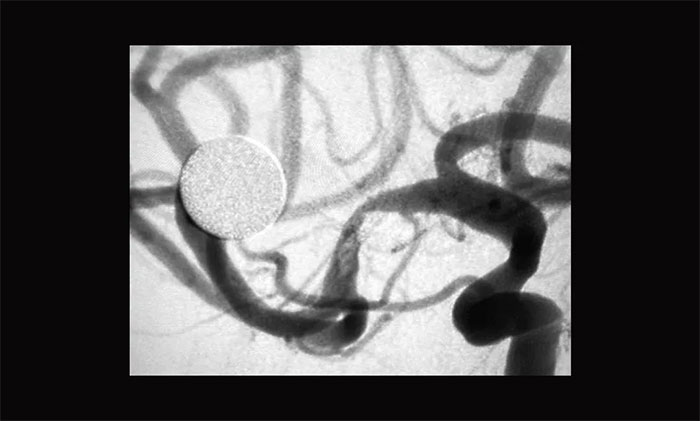

术中,经右侧桡动脉穿刺行全脑血管造影可见,右侧大脑中动脉MI段重度狭窄,约90%,远端血流缓慢,左侧椎动脉起始段迂曲,基底动脉冗扩。考虑患者反复出现脑梗死与右侧大脑中动脉狭窄有关,且其它血管对右侧大脑中动脉供血区域基本无代偿,一旦发生大脑中动脉闭塞将发生严重后果。遂决定行右侧大脑中动脉M1段球囊扩张术及取栓术。

▲ 术前DSA影像:右侧大脑中动脉MI段重度狭窄